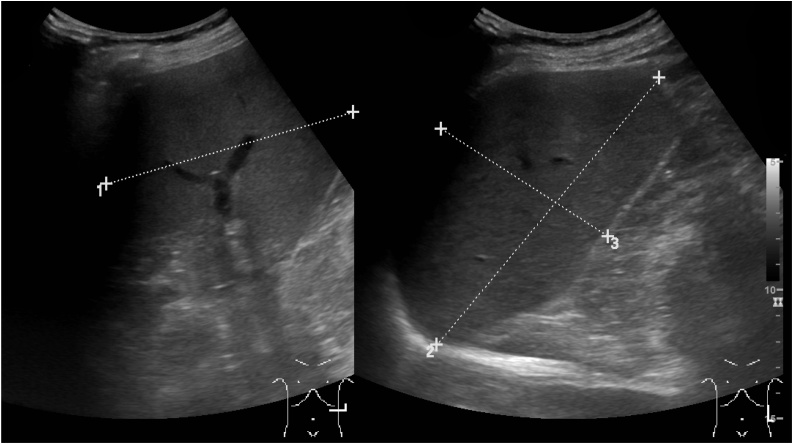

Fig. 2.

Sonography of the spleen two months prior to the atraumatic-pathological splenic rupture. Several hypoechogenic small areas were newly present.

The diagnosis of peliosis lienalis before histopathology is rarely possible. However, certain changes within the spleen on sonography or computed tomography could rise a suspicion [21]. In our case, there was a change noted within the splenic parenchyma a month prior to the rupture (Fig. 1, Fig. 2). This sonographic finding together with a progressive splenomegaly in patients with CMML have not been published before and we believe that this could alter the management of these patients towards more frequent observation or prophylactic splenectomy.